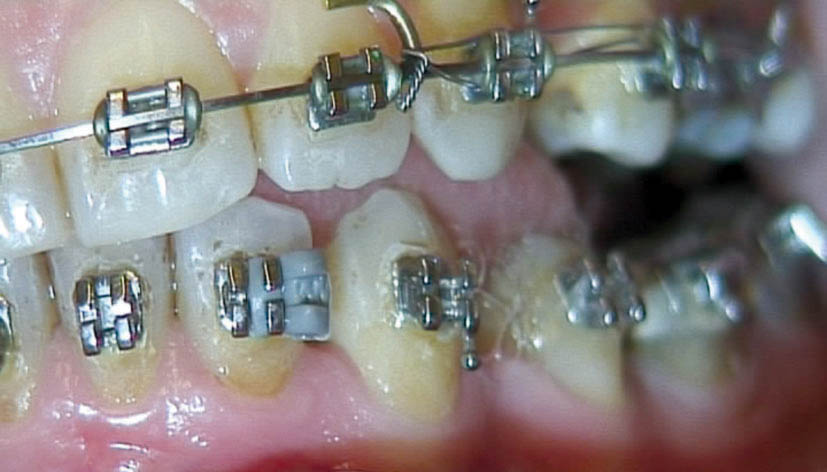

اگر در ابتدای درمان دیواره دیستالی به سمت لبیال چرخش داشته باشد باید روتیشنوج را بر روی بالچههای دیستالی بگذارید. اگر دیواره مزیالی به سمت لبیال چرخش داشته باید روتیشنوج را بر روی بالچههای مزیالی بگذارید، در این بیمار روی بالچههای دیستالی میگذاریم (شکل 171-1). بعد سیم 0.019x0.025 حرارتی را قرار دهید. شما نمیتوانید oring روی این براکت بیندازید، لذا وایر لیگاچور کنید. این روتیشنوج بایستی تا انتهای درمان بماند و همیشه روی براکت آن وایر لیگاچور شود (شکل 172-1). فقط در 4-2 هفته آخر که مرحله استقرار (فاز Settling) است باید آن را در بیاوریم تا قبل از خارج کردن براکتها، تمام دندانها مرتب باشند.

دقت شود برای اینكه روتیشنوج كارایی مناسبی داشته باشد باید حداقل به مدت شش ماه به كار رود.

شکل 171-1: بعد از مرتب شدن انسیزور در شکل 166-1، روتیشن وج روی نیمه دیستالی میگذاریم، بعد آرچ وایر 0.019x0.025 حرارتی را روی آن قرار میدهیم تا باعث لینگوالی شدن بیشتر دیستال آن بشود.

شکل 172-1: وقتی 0.019x0.025 استیل را میگذارید باید روتیشن وج بماند.